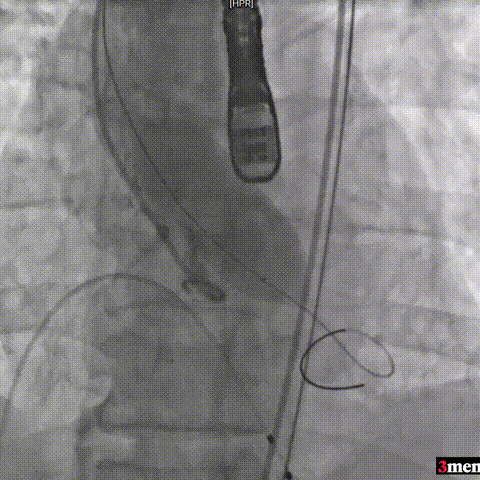

手术过程回顾:

患者全麻后,右侧股动脉建立主入路,主动脉根部造影显示主动脉瓣明显钙化。心室内轻微反流,主动脉及心脏情况整体较为稳定。直头导丝跨瓣后,在超硬导丝支撑下,瓣膜输送系统顺利跨瓣。在180次/分快速心室起搏下,确定降压至50mmHg后选择25mm球囊进行预扩张。根据术前评估及球囊预扩情况,最终选择直径29mm瓣膜进行植入。

主动脉根部造影

直头导丝跨瓣

球囊预扩

输送器过弓

输送器定位

瓣膜脱钩